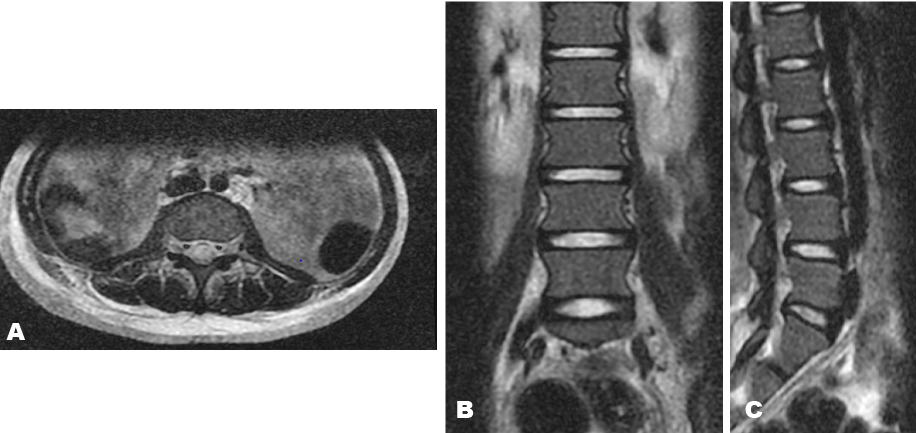

Complete blood count revealed hematocrit of 21%, total white cell count of 29.3x109/L (myeloblast 47%, neutrophil 29%, eosinophil 1%, lymphocyte 20%, monocyte 3%) and platelet 90x109/L. Peripheral blood film (PBF) showed leukocytosis with variable number of myeloblast (Figure 1A). Bone marrow aspiration (BMA) cytology showed a hypercellular marrow with maturation arrest along the myeloid cell line. The myelogram showed a myeloblast count of >20% with maturation arrest at the myelocytic stage, some of the blast cells contained Auer rods (Figure 1B), megakaryocytes were reduced. Both PBF and BMA were consistent with acute myeloid leukemia (AML) FAB M-4 subtype. Cerebrospinal fluid analysis (CSF) analysis was negative for malignant cells. A lumbosacral X-ray was normal. Magnetic resonance imaging of the lumbosacral region was obtained in the axial, sagittal and coronal view. Both T1- and T2-weighted sequences showed no signal intensity in the spinal cord, theca and cauda, with normal signal intensity involving the intervertebral disc (Figure 2).

Figure 2: T2-weighted lumbosacral magnetic resonance imaging (scan) in (A) Axial, (B) Coronal, (C) Sagittal view demonstrating no obvious cord pathology.

Several mechanism have been put forward to explain the pathogenesis of CNS involvement in leukemia, this include contamination of the CSF through the choroid plexus or infiltration of the cerebral parenchyma through brain capillaries; direct extension of aggregates of leukemic cells called chloroma, from the bone marrow through the cortical bones into the spinal cord, may cause symptoms as a result of mass effect on neural tissue [9]. Hyperleukocytosis with thrombosis may result in leukostasis and consequently poor CNS perfusion. Intracranial hemorrhage with focal neurological deficit may also arise. Hemorrhage into the spinal canal can occur following diagnostic procedures in cases presenting with thrombocytopenia [9]. In the index case, the CSF was negative for malignant cells and the MRI scan showed no obvious pathology. The presence of urinary and fecal incontinence indicates pathology involving the sacral canal. Relatively small tumor in this region may manifest with profound symptoms, unfortunately such tumors can be particularly difficult to image [9]. Consequently, the absence of findings on MRI scan does not completely exclude cord compression as seen in the index case report.